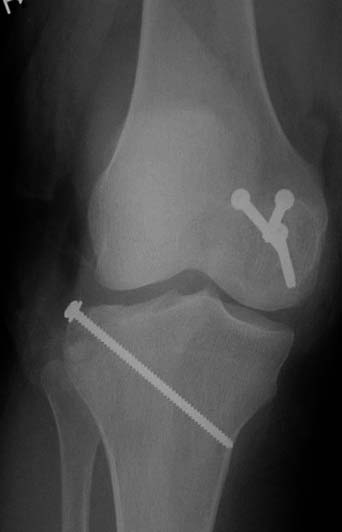

При изолированных переломах можно лечить миниинвазивно каннюлированными винтами, но в большинстве Hoffa компонент сопровождается другими типами перелома дистального бедра. Выбор доступа зависит от расположения фрагментов и большинстве латеральный субвастус доступ подойдет для фиксации перелома.

В данном случае предпочтителен парапателлярный доступ, где необходимо создать лучший обзор к мыщелку. После остеотомии и репозиции фиксацию надо проделать поперечными винтами и дополнительно задней antiglade plate - сделанной из 1/3 tubular plate.

Здесь представлены различные варианты фиксации перелома, а также снимки комбинации перелома с повреждением хряща (12-19). Пластика хряща OsseoFit и установка custom made plate.